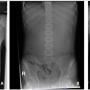

FIGURE 1: (A) Chest radiograph revealed an elevated left hemidiaphragm with absent of gastric bubble; (B) Abdominal radiograph revealed a paucity of small bowel gases that suggest proximal intestinal obstruction; (C) Chest radiograph taken post-intubation revealed bilateral alveolar opacities after the patient aspirated

Case Report Page 563 - 569

Fatal Wilkie’s Syndrome Complicated by Aspiration Pneumonia in an Adolescent with Autism: A Case Report